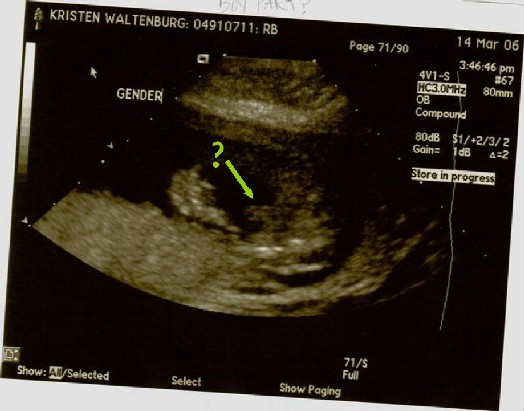

After following a strict schedule of how much water to drink, when to drink it, when to pee and when not to pee, Colby and I arrived at Kaiser for our big ultrasound appointment! The BIG day, when we would find out if we have a pink or blue bun in the oven!! While pacing up and down the aisle in a desperate attempt to stay in control of my bladder, my mom, Colby’s mom and his sisters join us for the long awaited peek. Finally! My name is called and I’m provided some relief as I lie down on the chair in the dark room. The nurse squirts some gel on my belly, which I was grateful to realize they warm it on this floor! She proceeds with the ultrasound, taking pictures for the doctor for about 20 minutes. I didn’t get a peek until the others were invited in. We saw distinct hands and feet, a big alien head, even an ear… but what we really wanted to see was obstructed by two little legs, crossed at the ankles. No angle could seem to enlighten us!! So, the nurse admitted that when she was taking pictures on her own, she got a possible view of what she thinks are boy parts, but since she couldn’t get back under there to verify it, she said she would print that picture and leave it to our interpretation. That’s where you come in. Please take a look at the pictures below. The one labeled “Gender” is the deciding factor. Once you’ve gotten a good look, please use the “post your comment” link at the bottom of this blog, and let us know if you believe it to be a boy or girl. Profile:

Boy Part?: (under buns view with legs sitting out to each side, green arrow pointing at the possible boy part)